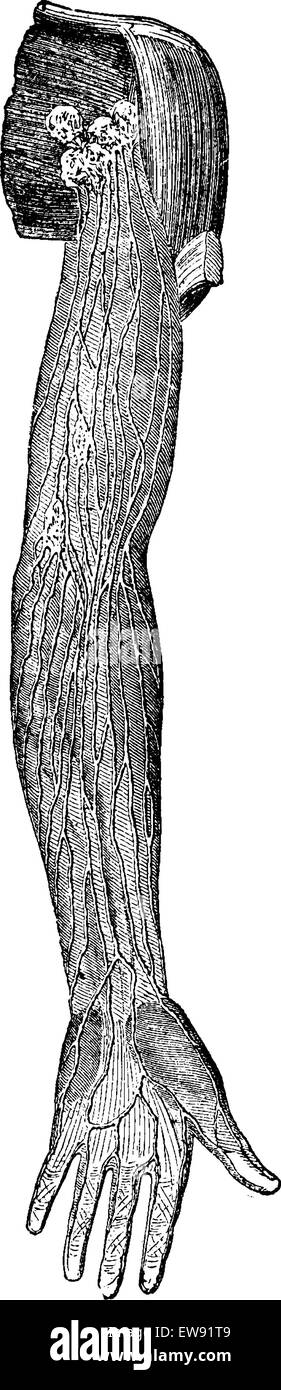

RFEW9HG6–Oberflächlichen Lymphgefäße der oberen Extremität, graviert Vintage Illustration. Üblichen Medizin Wörterbuch - Paul Labarthe - 1885

RFEW91T9–Oberflächlichen Lymphgefäße der oberen Extremität, graviert Vintage Illustration. Üblichen Medizin Wörterbuch - Paul Labarthe - 1885